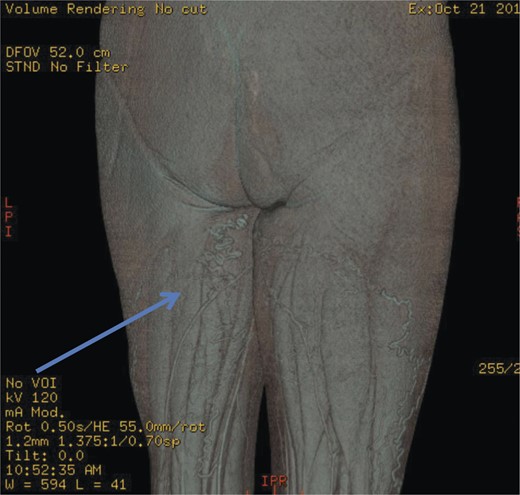

The superficial external pudendal vein was embolized with 1% sodium tetradecyl sulphate and then coiled through a contralateral puncture under fluoroscopic guidance (Figs 3 and 4). The procedure went uneventfully with successful obliteration of the communicating thigh veins to vulval varices (Fig. 5) and the patient was discharged home the same day.

Pre-embolization fluoroscopy showing communication of thigh veins to vulval varices (blue arrow).